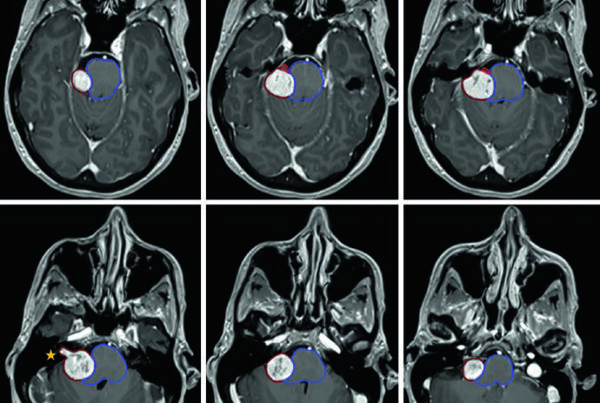

É importante observar que a lista da FDA inclui não apenas aplicações de software independentes, mas também equipamentos de imagem com IA embarcada — como sistemas de raios-X portáteis com algoritmos para detecção de condições emergenciais. Essa convergência entre hardware e software de IA está transformando o fluxo de trabalho radiológico, automatizando triagem e priorização de exames críticos.